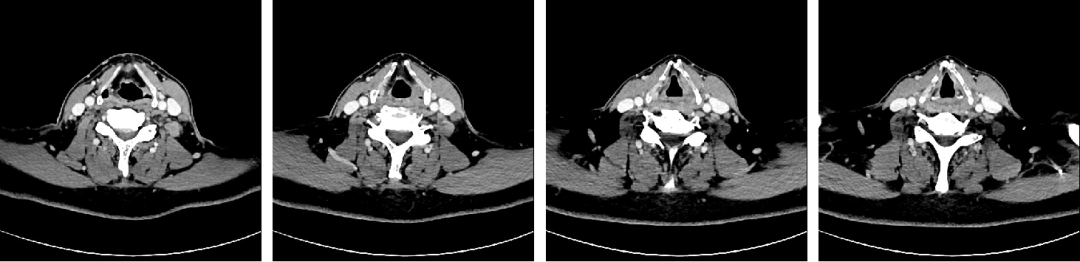

术前颈部增强CT检查(左侧梨状窝较右侧稍浅,左侧颈部多发肿大淋巴结伴强化)

诊断下咽恶性肿瘤(T1N2M0)